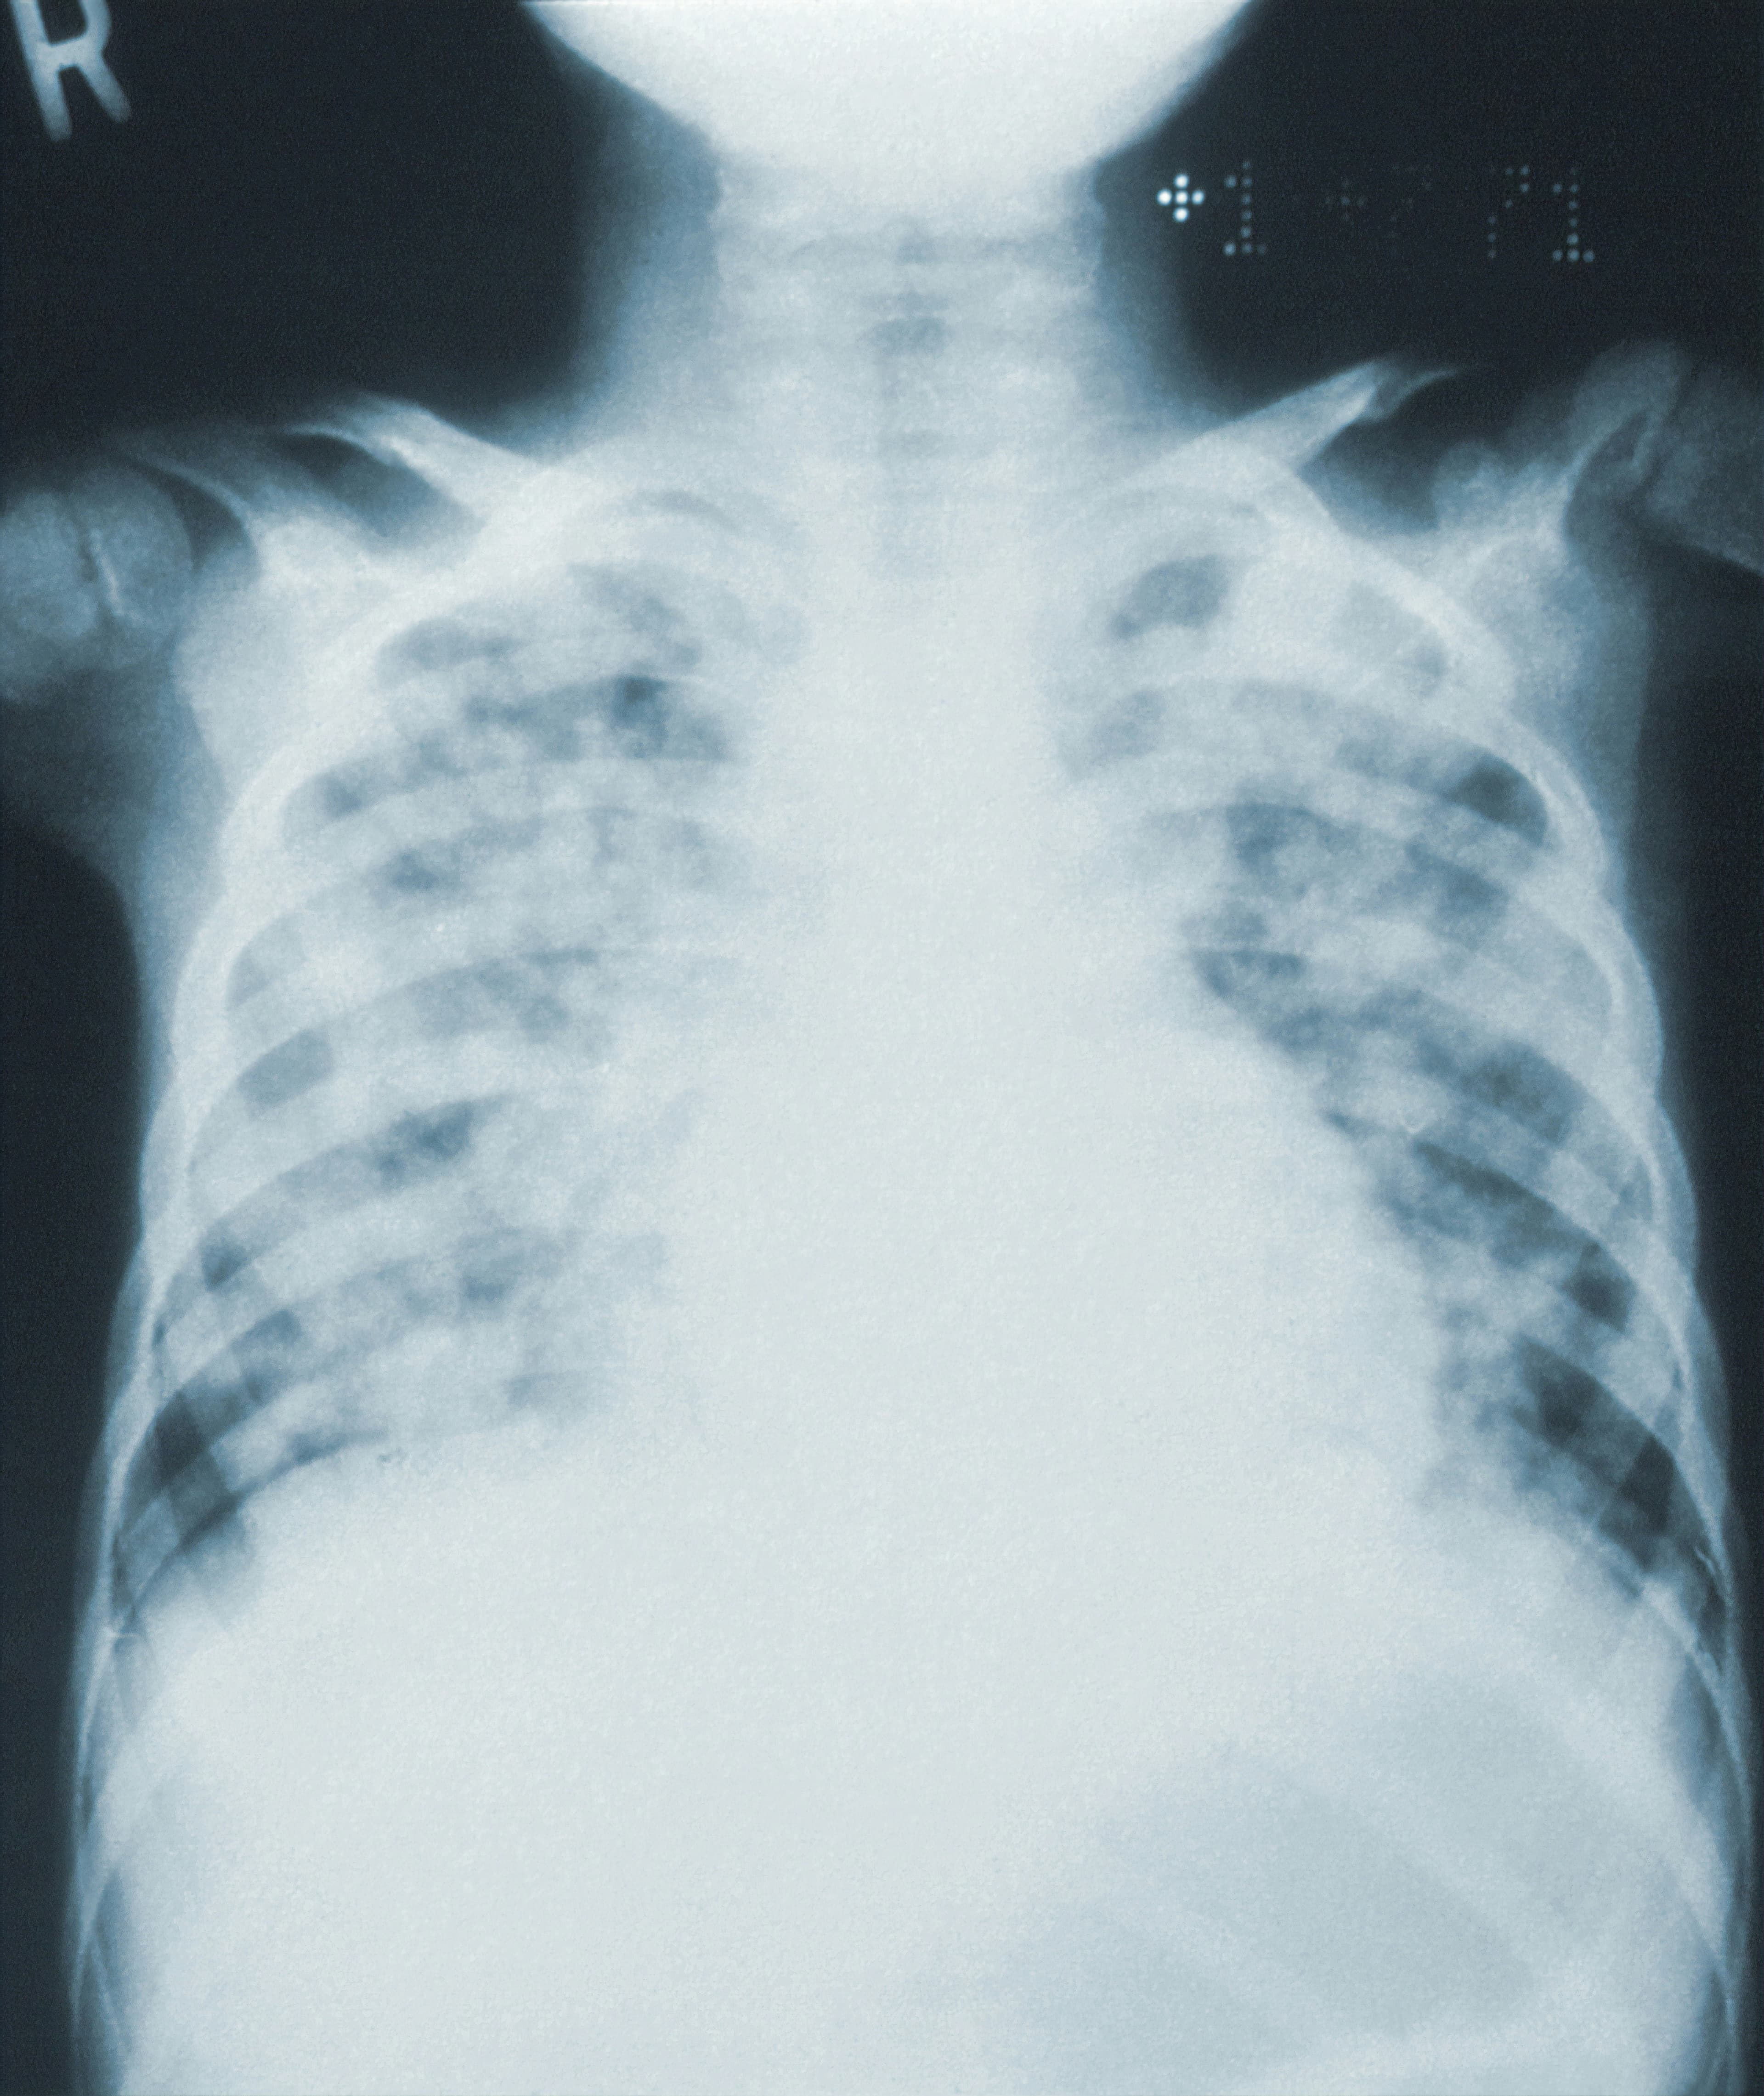

La computer vision a un bon potentiel pour identifier des personnes inconnues explorées en situation d’urgence. Une étude publiée dans la Revue European Radiology évalue l’efficacité du MIP par TDM thoracique pour que la computer vision puisse identifier des patients. Cette méthode est applicable à diverses reconstructions 2D grâce à des bases de données biométriques conséquentes.